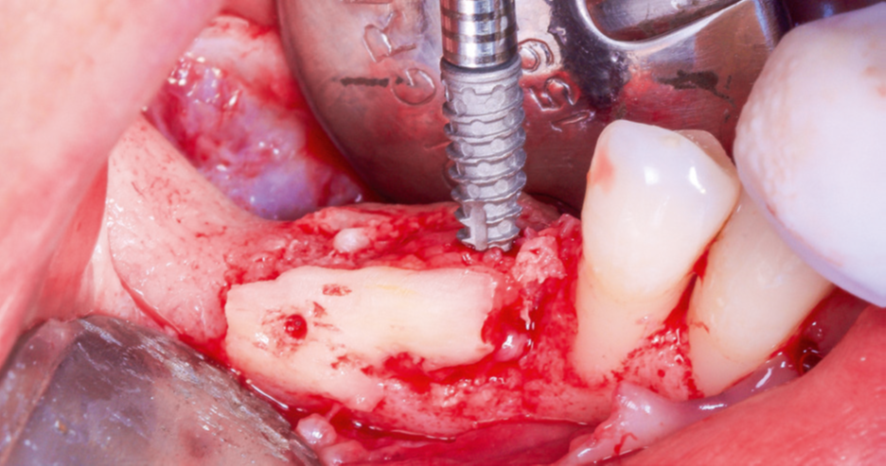

Após a maturação do tecido gengival, procedeu-se ao preparodo leito receptor com incisão e descolamento mucoperiosteal,liberando-se o tecido lingual por meio do alívio da tensão musculardo milo-hióideo (Figura 3) com o descolador de Molt (Supremo Instrumentais). Em seguida, prosseguiu-se com a coleta de osso autógeno do ramo mandibular (área próxima ao leito receptor, do mesmo lado, conforme Figura 4). As lâminas ósseas foram adaptadas e fixadas nas corticais vestibular e lingual com parafusos de titânio (Orth – Implacil Osstem / Figura 5), criando um compartimento do tipo caixa, preenchendo-se o seu interior com osso particulado autógeno (Figura 6). A sutura foi realizada com pontos em colchoeiro horizontal seguidos de pontos simples interrompidos (Figura 7). A cicatrização foi considerada satisfatória.

Figura 3 – Retalho, descolamento mucoperiosteal e liberação de tecido até ultrapassar o plano oclusal dos dentes adjacentes.

Figura 5 – Fixação das lâminas com técnica compressiva e parafusos Orth (Implacil Osstem).

Figura 6 – Preenchimento do “túnel” com osso autógeno particulado.